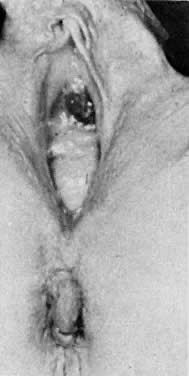

As many as 2 million pregnant women may have received synthetic estrogen compounds, predominantly diethylstilbestrol (DES), from the early 1940s through the early 1970s for prevention of miscarriage and other complications of pregnancy. In 1970, Herbst and Scully reported an alarming number of new cases of clear cell adenocarcinoma of the vagina.13 By 1971, Herbst and co-workers had associated these new cases of adenocarcinoma of the vagina with in utero exposure to DES.14 In 1987, Melnick and colleagues reported on 519 registered cases of clear cell adenocarcinoma of the cervix and vagina, with 60% of those patients exposed to DES in utero.15 Fortunately, the anticipated epidemic of adenocarcinoma of the cervix and vagina resulting from DES exposure did not develop. It is estimated that the risk of developing adenocarcinoma of the cervix or vagina as a result of DES exposure is 1 per 1000 exposed women.15 Nonmalignant structural changes of the cervix and vagina including cockscomb, cervical collar, cervical hood, pseudopolyp, and hypoplastic cervix have been described in 25% to 48% of in utero DES exposed women16 (Fig. 6). Vaginal epithelial changes, predominantly adenosis has been reported in 34% to 65% of in utero exposed women17 (Fig. 7, Fig. 8). Adenosis may be described as the retention of mu¨llerian-derived glandular epithelium in the vagina after vaginal embryogenesis is completed18 (Fig. 9). The evaluation of the DES exposed patient includes careful palpation of the entire vagina searching for any submucosal nodularity which would lead to biopsy. This is followed by careful colposcopic examination of the entire vagina with special attention to the upper third, looking for characteristic changes of columnar epithelium. Cytologic samples are taken from the cervix and vagina. Structural changes of the cervix and vagina are noted. Finally, the entire vagina is stained with Lugol's solution and re-examined to search for any nonstaining areas (Fig. 10). Biopsy is performed on any nonstaining areas, palpable nodules, and colposcopically detected columnar epithelium in the vagina. Biopsies confirm the presence of adenosis and exclude more significant lesions. This extensive evaluation is performed on the first visit and does not need to be repeated. Annual exams including cytologic evaluation and palpation of the cervix and vagina are proposed to the patient with a negative initial evaluation. Once diagnosed, adenosis is observed without therapy. In most cases, adenosis will resolve as a result of squamous metaplasia. Recently, vaginal adenosis has been reported as a result of laser therapy of the vagina for condyloma or dysplasia.19 This should not be confused with DES related adenosis.

Fig. 6. Cervical-vaginal hood in patient with antenatal exposure to synthetic estrogen.